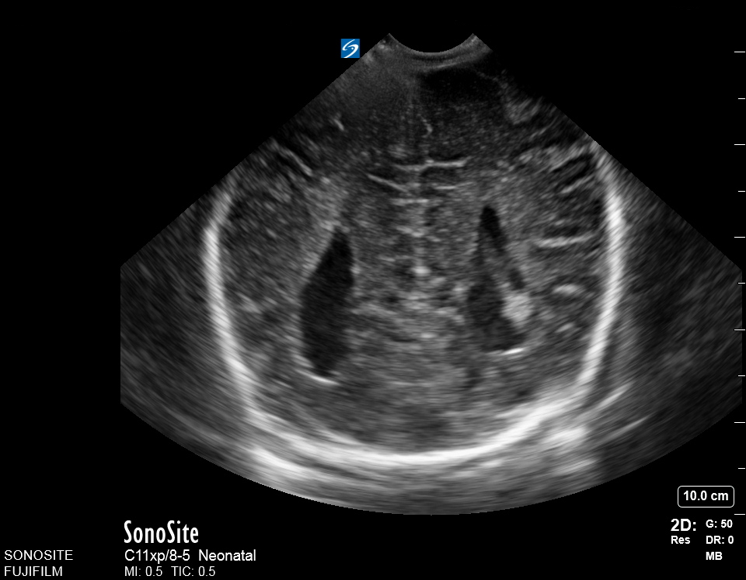

Neonatology Corpus Callosum Agenesis 5 Image